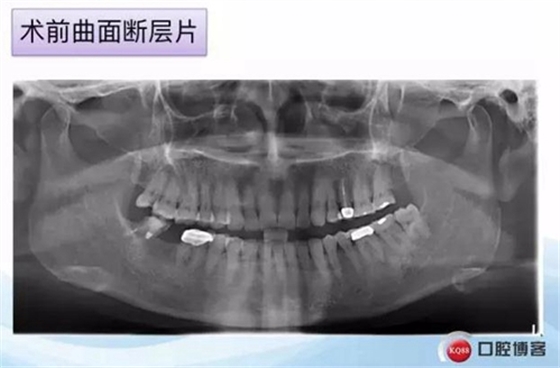

一例后牙常規(guī)種植病例 科貿(mào)嘉友收錄